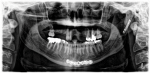

A male patient visited prosthodontist Young S. Kang, DDS, FACP, for restoration of the missing front teeth (Figure 1). Three years prior to the initial visit, the patient suffered multiple fractures to the head, including bilateral subcondylar fractures and bilateral coronoid fractures, from a motor vehicle accident. During the recovery period, the patient underwent extensive dental treatments (Figure 2 through Figure 4).

Based on the diagnostic wax-up (Figure 6) and other clinical findings, the prosthodontist made the following diagnosis: (a) partial edentulism with missing teeth Nos. 3 through 5 and 8 through 12 (Kennedy Class 3 mod I1); (b) irregular plane of occlusion due to supra-eruption of teeth Nos. 29 and 30; (c) low horizontal condylar inclination of the right condyle (5° vs. 42° of the left condyle); and (d) moderate tooth wear (Smith and Knight Class Two2).